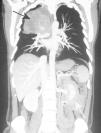

Fig. 1. Reconstrucción coronal tras estudio de tórax, abdomen y pelvis con contraste intravenoso utilizando un equipo de tomografía computarizada de 64 detectores. Se observan una masa en el lóbulo superior derecho (flecha negra) y un engrosamiento de asas de intestino delgado (flecha blanca), debido a un carcinoma primitivo de pulmón neuroendocrino con metástasis intestinales.